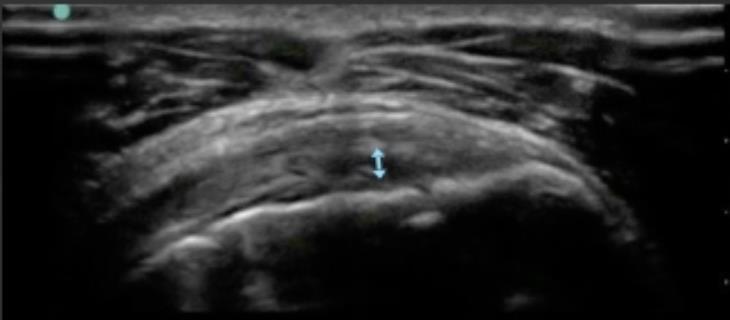

Shoulder Abnormal Infraspinatus Tendon 2 Image